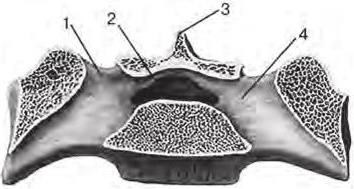

Анатомия: Межкорневая костная перегородка